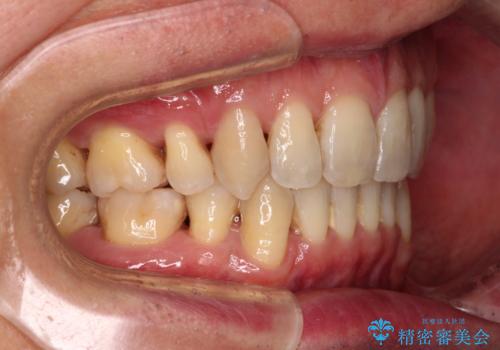

- 口元の閉じにくさと、前歯のでこぼこの歯並びを気にして来院された患者様です。

口元を積極的に引っ込めるために、上下左右の小臼歯計4本を抜歯することとしました。

叢生が強い場合、抜歯スペースが叢生を解消するために消費されるため、口元の突出感があまり改善されないことがあります。

今回の治療では、奥歯が前方に傾斜した歯並びだったため、奥に起き上がることで歯列が後方に移動し、横側からも口元が引っ込んだ感じが分かるほど改善されました。